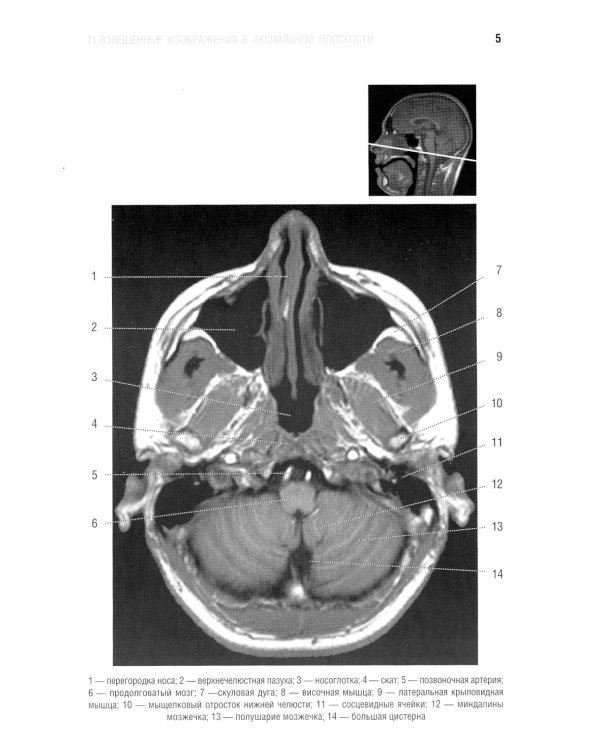

В руководстве представлена нормальная анатомия головного мозга и позвоночника по данным МРТ- и КТ-исследований. MPT-изображения головного мозга отражены в трех взаимно перпендикулярных плоскостях. Отдельная глава посвящена визуализации и нормальной анатомии сосудов головного мозга, в том числе с изображениями, получаемыми при бесконтрастной магнитно-резонансной ангиографии. Для врачей-рентгенологов, специалистов КТ и МРТ, невропатологов, нейрохирургов, а также врачей смежных специальностей. Руководство рекомендовано для обучения студентов медицинских вузов, а также может использоваться в системе последипломного профессионального образования.| Издательство | Элби |